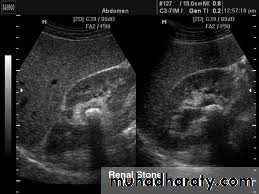

32- Stone

35- Stone without hydronephrosis (left) and stone with hydronephrosis (right)

36- Hydronephrosis